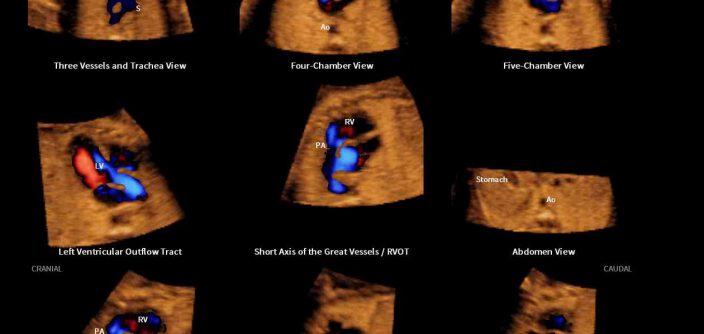

Professor Lami Yeo, M.D., from the Department of Obstetrics and Gynecology at the Wayne State University School of Medicine in Detroit, U.S., presented research on the diagnostic performance of Fetal Intelligent Navigation Echocardiography (5D Heart™) which showed a sensitivity of 98%, specificity of 93%, and accuracy of 95% for the prenatal detection of congenital heart disease*. She also explained that 5D Heart™ offers a rapid and simple solution to screen for and diagnose congenital heart disease by generating nine standard fetal echocardiography views in a single template display.

Additionally, novel research conducted on color Doppler Fetal Intelligent Navigation Echocardiography (5D Heart Color™) will be published in the October 2017 issue of the scientific journal Ultrasound in Obstetrics & Gynecology (UOG), which will also feature on its front cover, the prenatal diagnosis of congenital heart disease using 5D Heart color™.